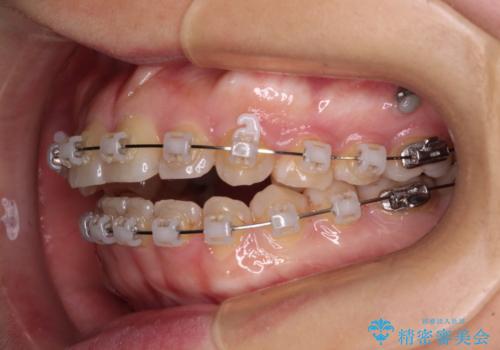

- クリアブラケット

- 1年7ヶ月

舌の突出癖により上下前歯が開咬となりましたが、舌のトレーニングと顎間ゴムの使用により、元々の被蓋関係に改善することができました。

アンカースクリューを用いて、出っ歯仕上がりを回避し、正中位置も改善することができました。